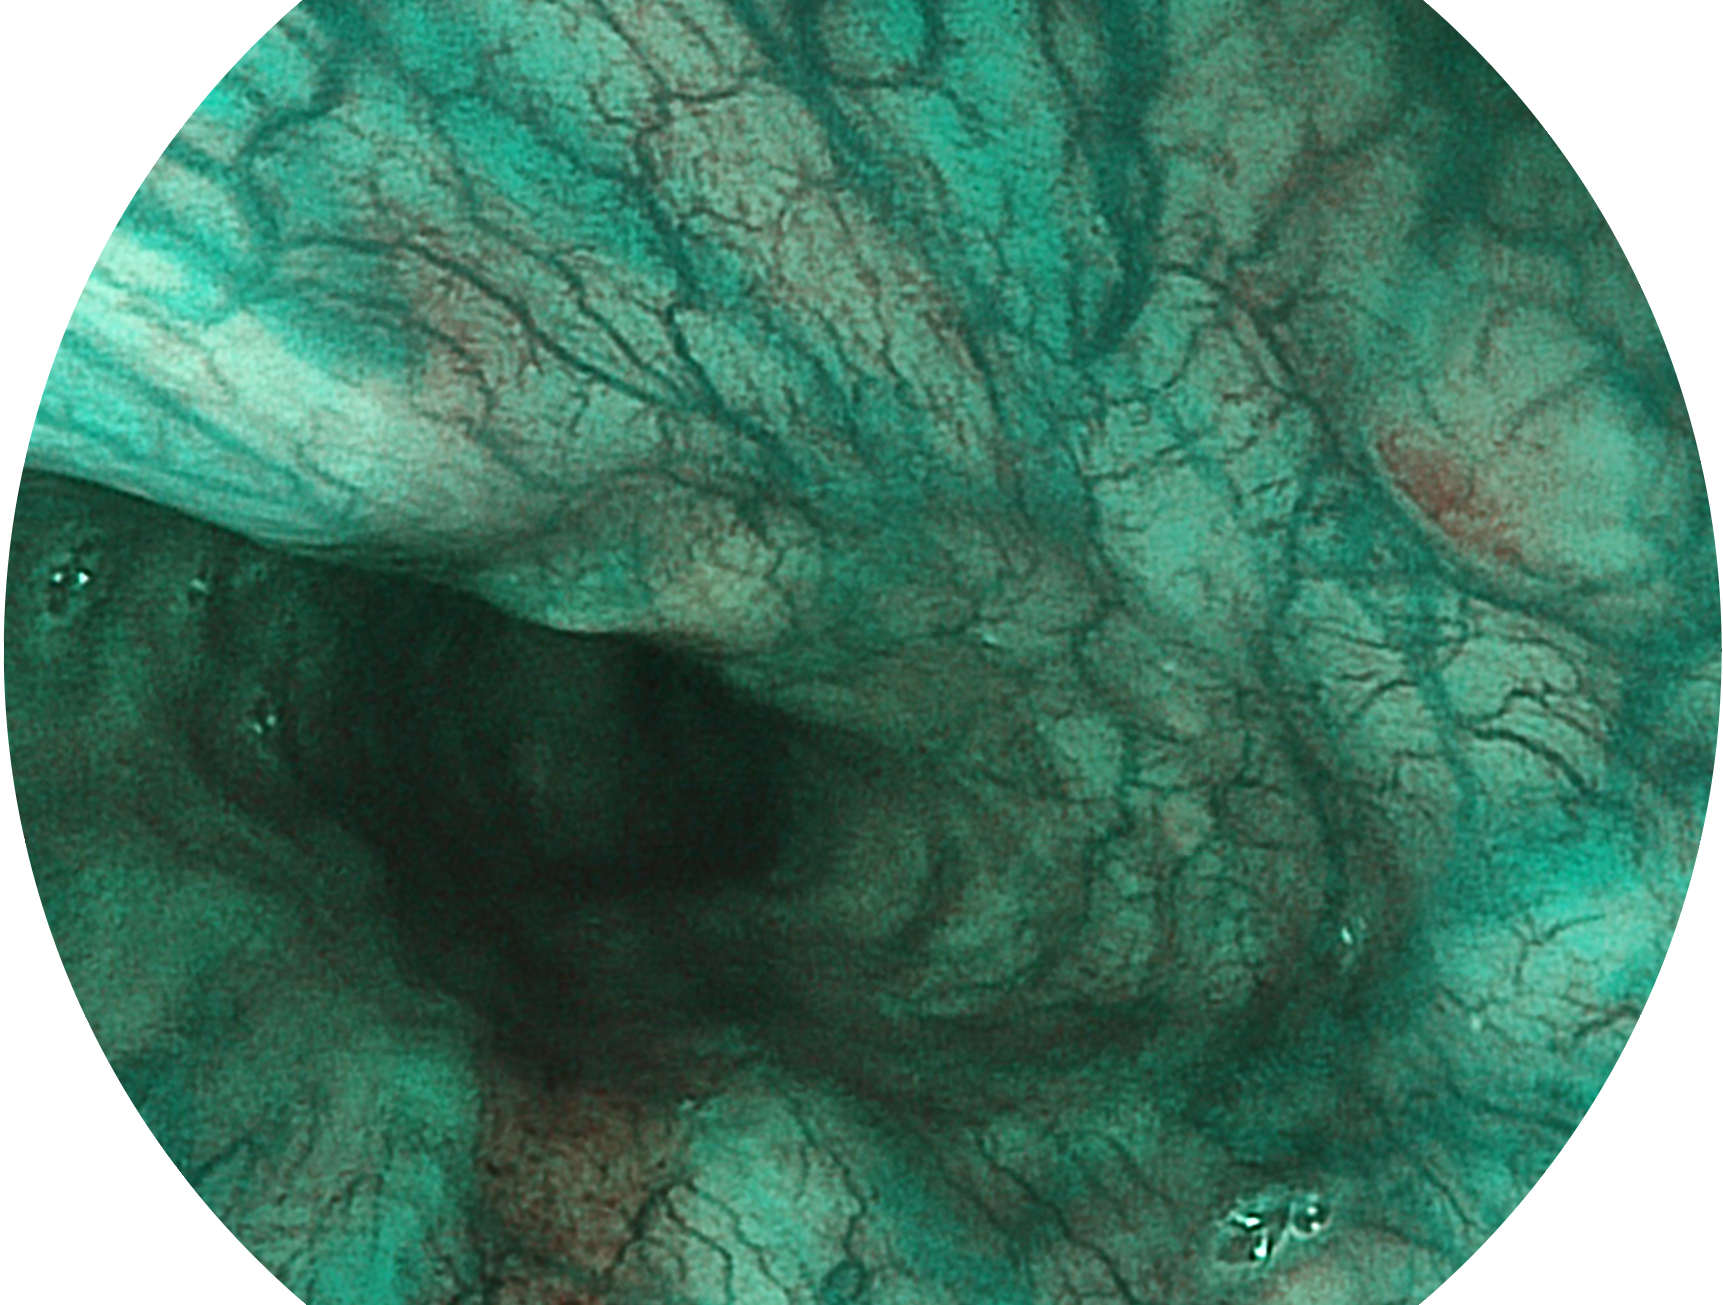

1xBET新开发的内镜染色技术,主要是基于多波长LED 光源的开发,VLS-55Q 四波长LED 光源是由四个不同颜色的LED光按照相应照明模式所规定的特定发光比例进行合束后形成,合束后形成的照明光的光谱由红光、绿光、蓝光及蓝紫光这四个不同的波段范围构成。具有更高光谱自由度,通过光谱比例的控制,实现了聚谱成像技术,英文全称为“Spectral Focused Imaging, SFI”,缩写为“SFI”和光电复合染色成像技术,英文全称为“Versatile Intelligent Staining Technology, VIST”,缩写为“VIST”。